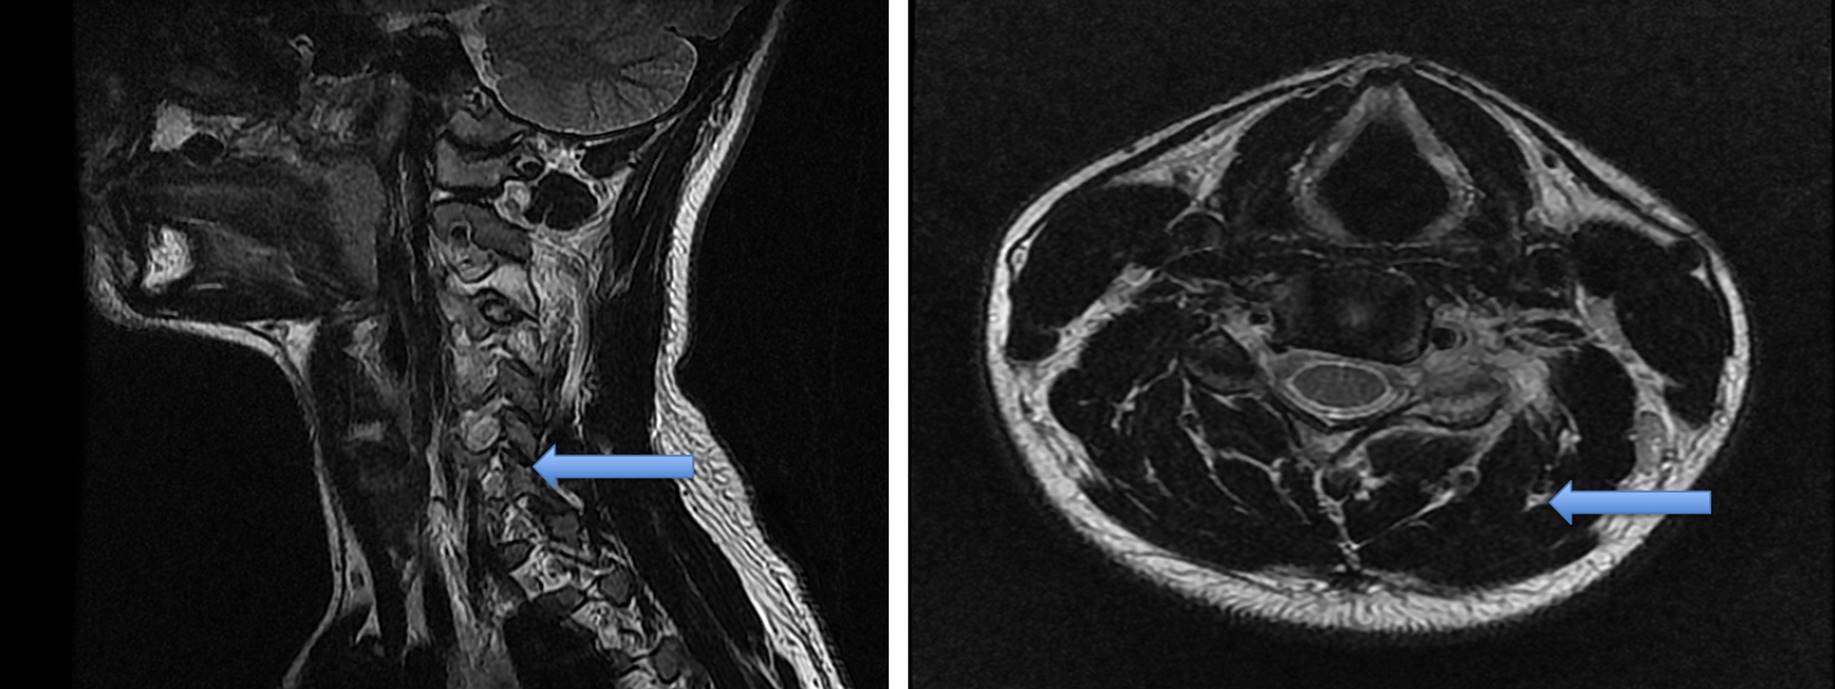

Resonancia magnética posquirúrgica (después de cirugía extrainstitucional)

Las imágenes tomadas revelan cambios posquirúrgicos de resección de masa en la apófisis articular superior izquierda de C4. Se observó una lesión expansiva de señal intermedia en T1, con realce algo heterogéneo con gadolinio, con medidas aproximadas de 14 × 16 × 17,5 mm, considerada primera posibilidad residuo o recidiva de la lesión. No se detalló alteración en la amplitud del canal espinal, con cuerpos vertebrales y discos intervertebrales sin alteraciones.

La imagen en T2 evidenció un aumento en la intensidad de señal de los músculos paravertebrales izquierdos entre C3-C4 y C4-C5, atribuidos a cambios por el procedimiento quirúrgico, relativamente reciente en el momento de toma de la imagen (figuras 4 y 5).